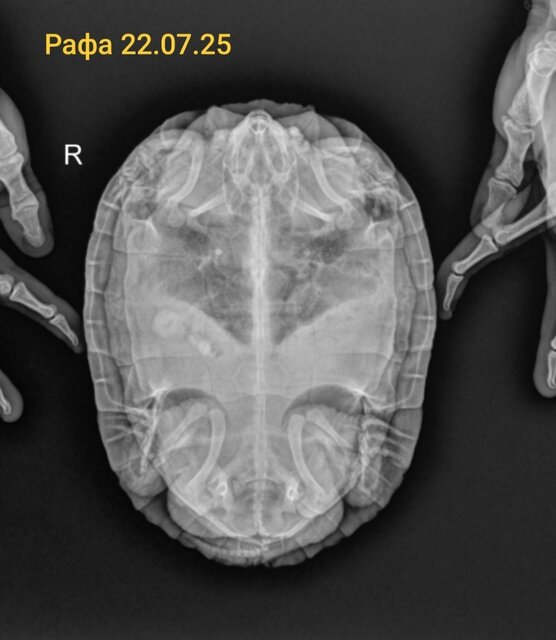

Но сегодня она при мне снесла яйцо без скорлупы, просто в оболочке. Питание основа рептамин, рыба/насекомые раз в месяц. УФ Рептиспа 10 увб 26вт работает 6,5 месяцев. На днях поставила новые уф. По анализам, которые сдавали 2 месяца назад, черепаха здоровая. Была задержка с выходом яиц, тк из в два раза больше,чем прошлые кладки, и на всякий случай прокололи курс на кальция 10 уколов месяц назад по рекомендации врача. Второй рентген в этом году было 19 яиц перед уколами кальция, после него уже вышло 27 яиц.

По рентгену яиц нет, со слов специалиста проводившего УЗИ: по УЗИ три яйца и небольшое скопление жидкости в брюшной полости и воспаление. Полное описание УЗИ мне ещё не прислали, тк мы приехали без записи и в порядке очереди ждали когда освободится специалист и примет нас.

@Sonya5555 интересно, что по рентгену яиц нет, а по узи есть. Если только они там такие же без скорлупы.

А по структуре костей нет описания о дефиците кальция? я к сожалению не умею в этой области снимки читать.

@moth скорее всего да, тоже безскорлупные. Про структуру костей завтра уточню у рентгенолога, спасибо!